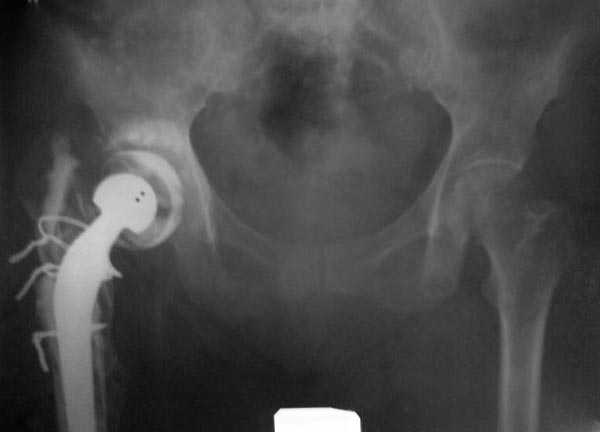

Вот снимки по свежей ситуации, парень 19 лет, длинный оскольчатый перелом бедра от шейки до в-с/3. давно уже ходит на своих ногах.

Представленные Вами рентгенограммы действительно являются примером качественной фиксации спице-стержневым аппаратом. Они, как ни что другое, многое иллюстрируют.

Кроме того, было бы ошибкой ставить знак равенства между нашим и Вашим пациентами. Они не только не похожи, разница между ними просто огромная. Говорю это не для того, чтобы задеть Вас или обидеть. Ни в коем случае. Просто теперь я понимаю, что Ваше мнением строится на простом преломлении Ваших подходов к лечению пациентов со свежими переломами, на ситуацию, абсолютно несопоставимую, подобную нашей.